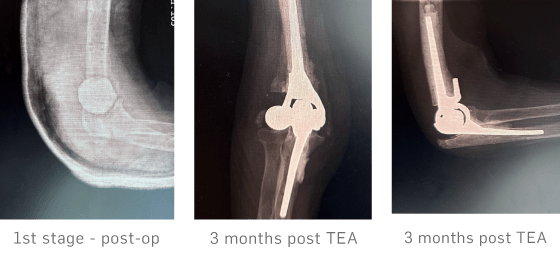

A staged surgical approach was adopted. Stage 1 involved removal of all metalwork, multiple tissue and bone samples for microbiological analysis, extensive debridement of necrotic bone and heterotopic ossifications, thorough lavage, and insertion of an antibiotic-loaded cement spacer along with 10 cc of STIMULAN mixed with antibiotic and made into beads. The patient commenced empiric intravenous antibiotics via a PICC line, which were continued for two weeks until culture results confirmed no bacterial growth.

After a 3 month interval, Stage 2 was performed, consisting of a total elbow arthroplasty (TEA).

At the 3 month post-operative review, radiographs showed complete resorption of the STIMULAN beads and satisfactory integration of the prosthesis without evidence of loosening or subsidence. Clinically, the surgical scar was well healed, with restoration of functional, pain-free elbow movements. The patient reported marked improvement compared with her preoperative status, and there were no clinical or radiological signs of infection.